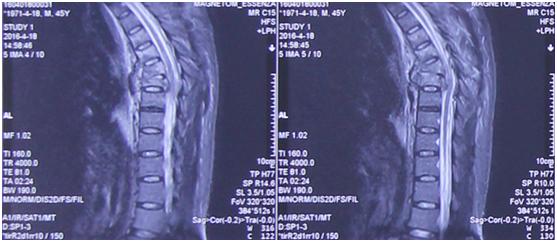

入院后,唐都医院神经外科给予高度重视,积极行术前检查。神经外科脊柱脊髓疾病治疗组组长李维新教授*析王分**先生影像学检查资料,指出“从患者影像学资料来看,1.胸6、7椎体骨折,脊髓轻度受压;2.胸6、7椎体爆裂性骨折,颈7椎体棘突骨折,左侧1、2肋骨及右侧第6肋骨骨折。”

影像学资料

“当患者入院后,我们发现整个脊柱已经完全断掉,而且不是一个横断,是一个斜型的断裂,斜向骨折线上下两个椎体已经完全错开。”李维新教授表示:“这种高能量损伤对脊柱损伤非常大,同时伴有大量的血气胸,病人呼吸困难生命垂危,因为胸腔里全是血,脊髓也受到严重的挫伤,造成患者脊柱损伤的话这个力量是非常大的。”